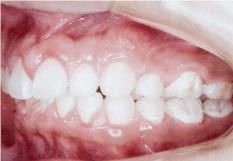

- 上顎前突(じょうがくぜんとつ)

- 上の歯が前面に傾斜して生えている状態です。または下の歯全体が後ろに位置することでも出っ歯に見えます。

この状態だと前歯でくちびるを切ってしまったり、顔を強打したときに歯が折れやすくなります。 - 下顎前突(がかくぜんとつ)